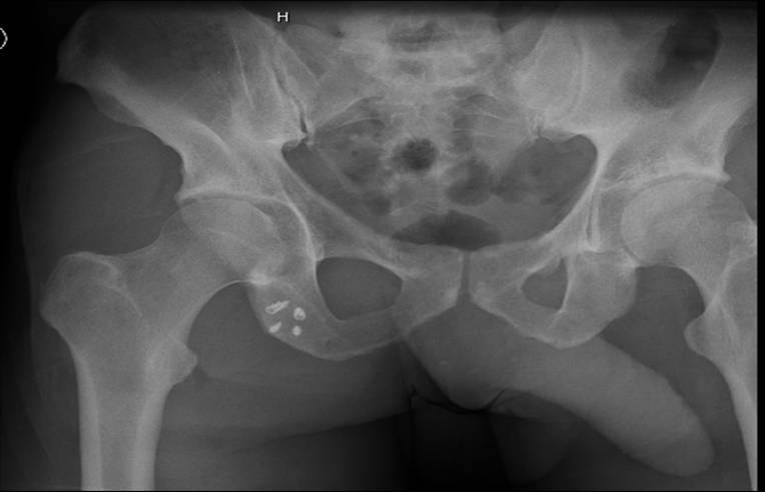

Xray

Exclude bony avulsion

Proximal hamstring avulsion on right - red circle is retracted hamstring tendon, blue circle is normal insertion on left

Proximal hamstring avulsion, with tendon floating in hematoma / seroma